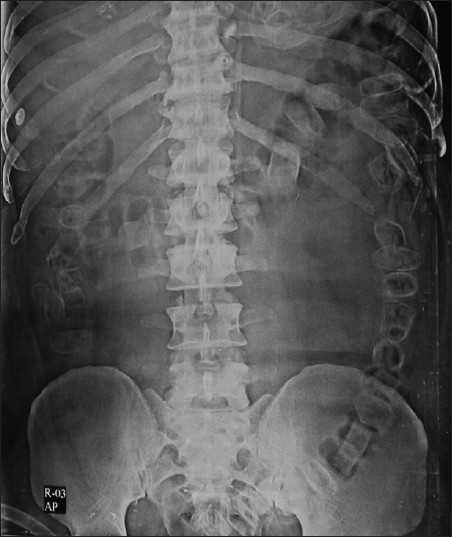

Bác sĩ sau khi chụp X-quang cho biết phần bụng bà cụ có quá nhiều phân cần phải thông trực tràng ngay. Khi thực hiện thủ thuật xuất hiện các tia máu chảy ra theo phân làm bác sĩ nghi ngờ có dị vật đường ruột nên tiếp tục sử dụng nội soi đại tràng nhưng không phát hiện bất thường.

| Hình ảnh táo bón chụp bằng X-quang. Ảnh: EBC. |